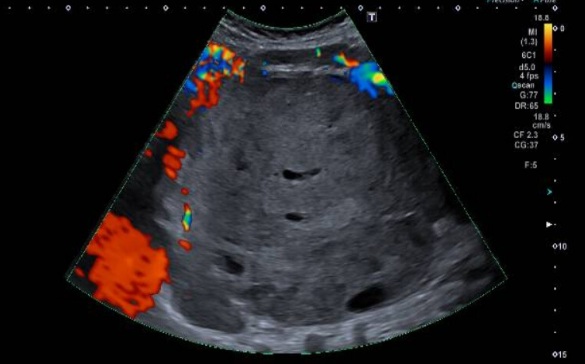

3. ECOGRAFÍA ABDOMINAL

Ecografía abdominal: Voluminosa masa sólida heterogénea, con áreas quísticas, que

se extiende desde el hipocondrio izquierdo hasta fosa ilíaca izquierda. Impresiona de

origen renal. Presenta vascularización periférica al examen Doppler color. En hilio renal

derecho se observa imagen de similares características y de menor tamaño.